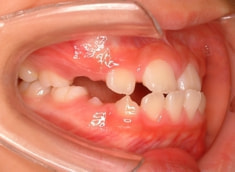

小児期ケース:反対咬合(受け口)

治療期間:1年3ヶ月

治療分析:日本人の反対咬合や下顎前突は、上顎の劣成長を伴なうことが多いので、上顎を側方拡大と前方に牽引しました。側方拡大方法は急速拡大で、正中口蓋縫合の拡大を行い、横口蓋縫合を剥がす効果で、前方牽引の効果を促進します。

治療後(1年3ヶ月後)